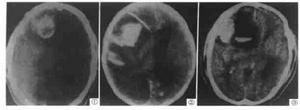

在出血急性期CT片上呈現高密度影,周圍低密度或等密度區,伴有占位效應,強化後呈不同程度的不規則密度影慢性期隨血腫的液化吸收,出血的高密度灶轉為等密度或低密度但CT對位於顱底或後顱凹的病變欠敏感、有時不能將腫瘤內多發性小鈣化斑與小出血灶區別開來。磁共振是目前有效的影像診斷手段它不僅對出血的類型,而且對血腫的轉歸均能準確診斷能診斷CT所不能確診的病變,特別是對於腦血管畸形的鑑別診斷明顯優於CT。此外,對於血圖像運豐富的腫瘤應進一步行腦血管造影。